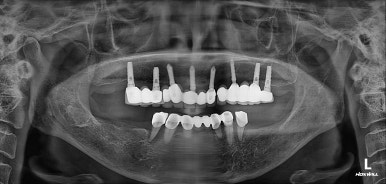

처음 아래 부분틀니를 제작할 당시에 여러개의 치아를 보철물로 묶어서 제작해드렸어야 하는데, 보시다시피 single crown으로 제작되어있는지라 성인 여성의 저작력을 견디지 못하고 만성치주염으로 흔들거리는 상태가 되었죠... 보면 치과용 파노라마 사진에서 두 치아 주변으로 까맣게 잇몸뼈 소실이 관찰됩니다.

위턱은 임플란트로 어느 정도 치아 자리가 채워져 있는 모습이지만, 아래턱은 어금니가 상당히 많이 없네요.

임플란트로 모두 치료해보기로 하였습니다.

수술 후 촬영한 치과용 파노라마 사진에서, 정~말 깔끔하고 예쁘게 식립된 임플란트를 보실 수 있습니다.

아래턱뼈 내부에는 하치조신경이라는 감각신경이 주행하고 있는데요, 네비게이션 임플란트를 통해 수술 후 감각마비 없이 깔끔하게 마무리 되었습니다.

치과용 파노라마 사진을 보면 뭔가 좌우 대칭으로 깔끔하게 완성된 아래턱 양쪽 어금니 임플란트를 보실 수 있어요!!

치과용 파노라마 엑스레이만 보아도, 임플란트 여섯개가 깔끔하게 제작된 것을 보실 수 있을겁니다.